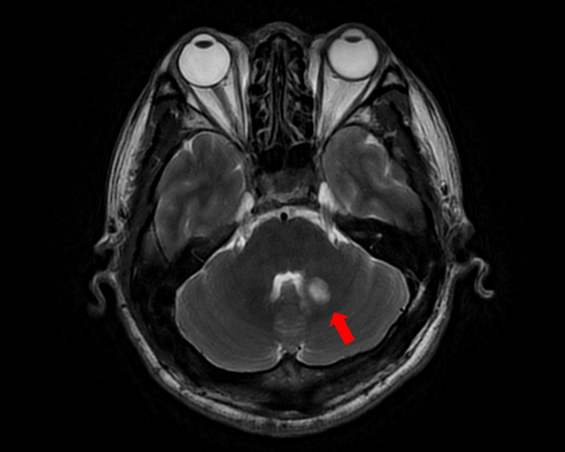

随着患者高先生颅内中脑左侧、左侧小脑两处病灶的顺利切除,国际神经外科医生集团专家已累计在苏大附四院完成了第100例高难手术。这标志着我院在神经外科国际化合作交流方面取得了里程碑式的成果,也为众多疑难脑肿瘤患者带来了新的希望。

自苏州大学附属第四医院与国际神经外科医生集团签约合作以来,Bertalanffy(巴特朗菲)教授、Froelich(福洛里希)教授等专家已多次来院开展深度医疗合作。在手术室里,国际专家与我院神经外科团队紧密配合,针对脑干、丘脑、颅底等高难度区域的复杂肿瘤,实施了包括脑干海绵状血管瘤、颅底脑膜瘤、复杂胶质瘤等一系列高风险手术。百例手术,不仅是数字的积累,更是技术与信任的双重见证。

苏州大学附属第四医院始终坚持走国际化、高水平发展道路。通过江苏省卫生支撑计划及中德国际合作交流项目,医院成功搭建了高端国际医疗合作平台。在多个项目以及平台的带动下,我院神经外科团队已能独立开展脑干海绵状血管瘤、脊髓髓内肿瘤、复杂颅底肿瘤等以往被视为“手术禁区”的高难度手术,整体技术水平迈上新台阶。科室在疑难重症诊疗、微创手术应用、神经功能保护等方面形成了鲜明特色。